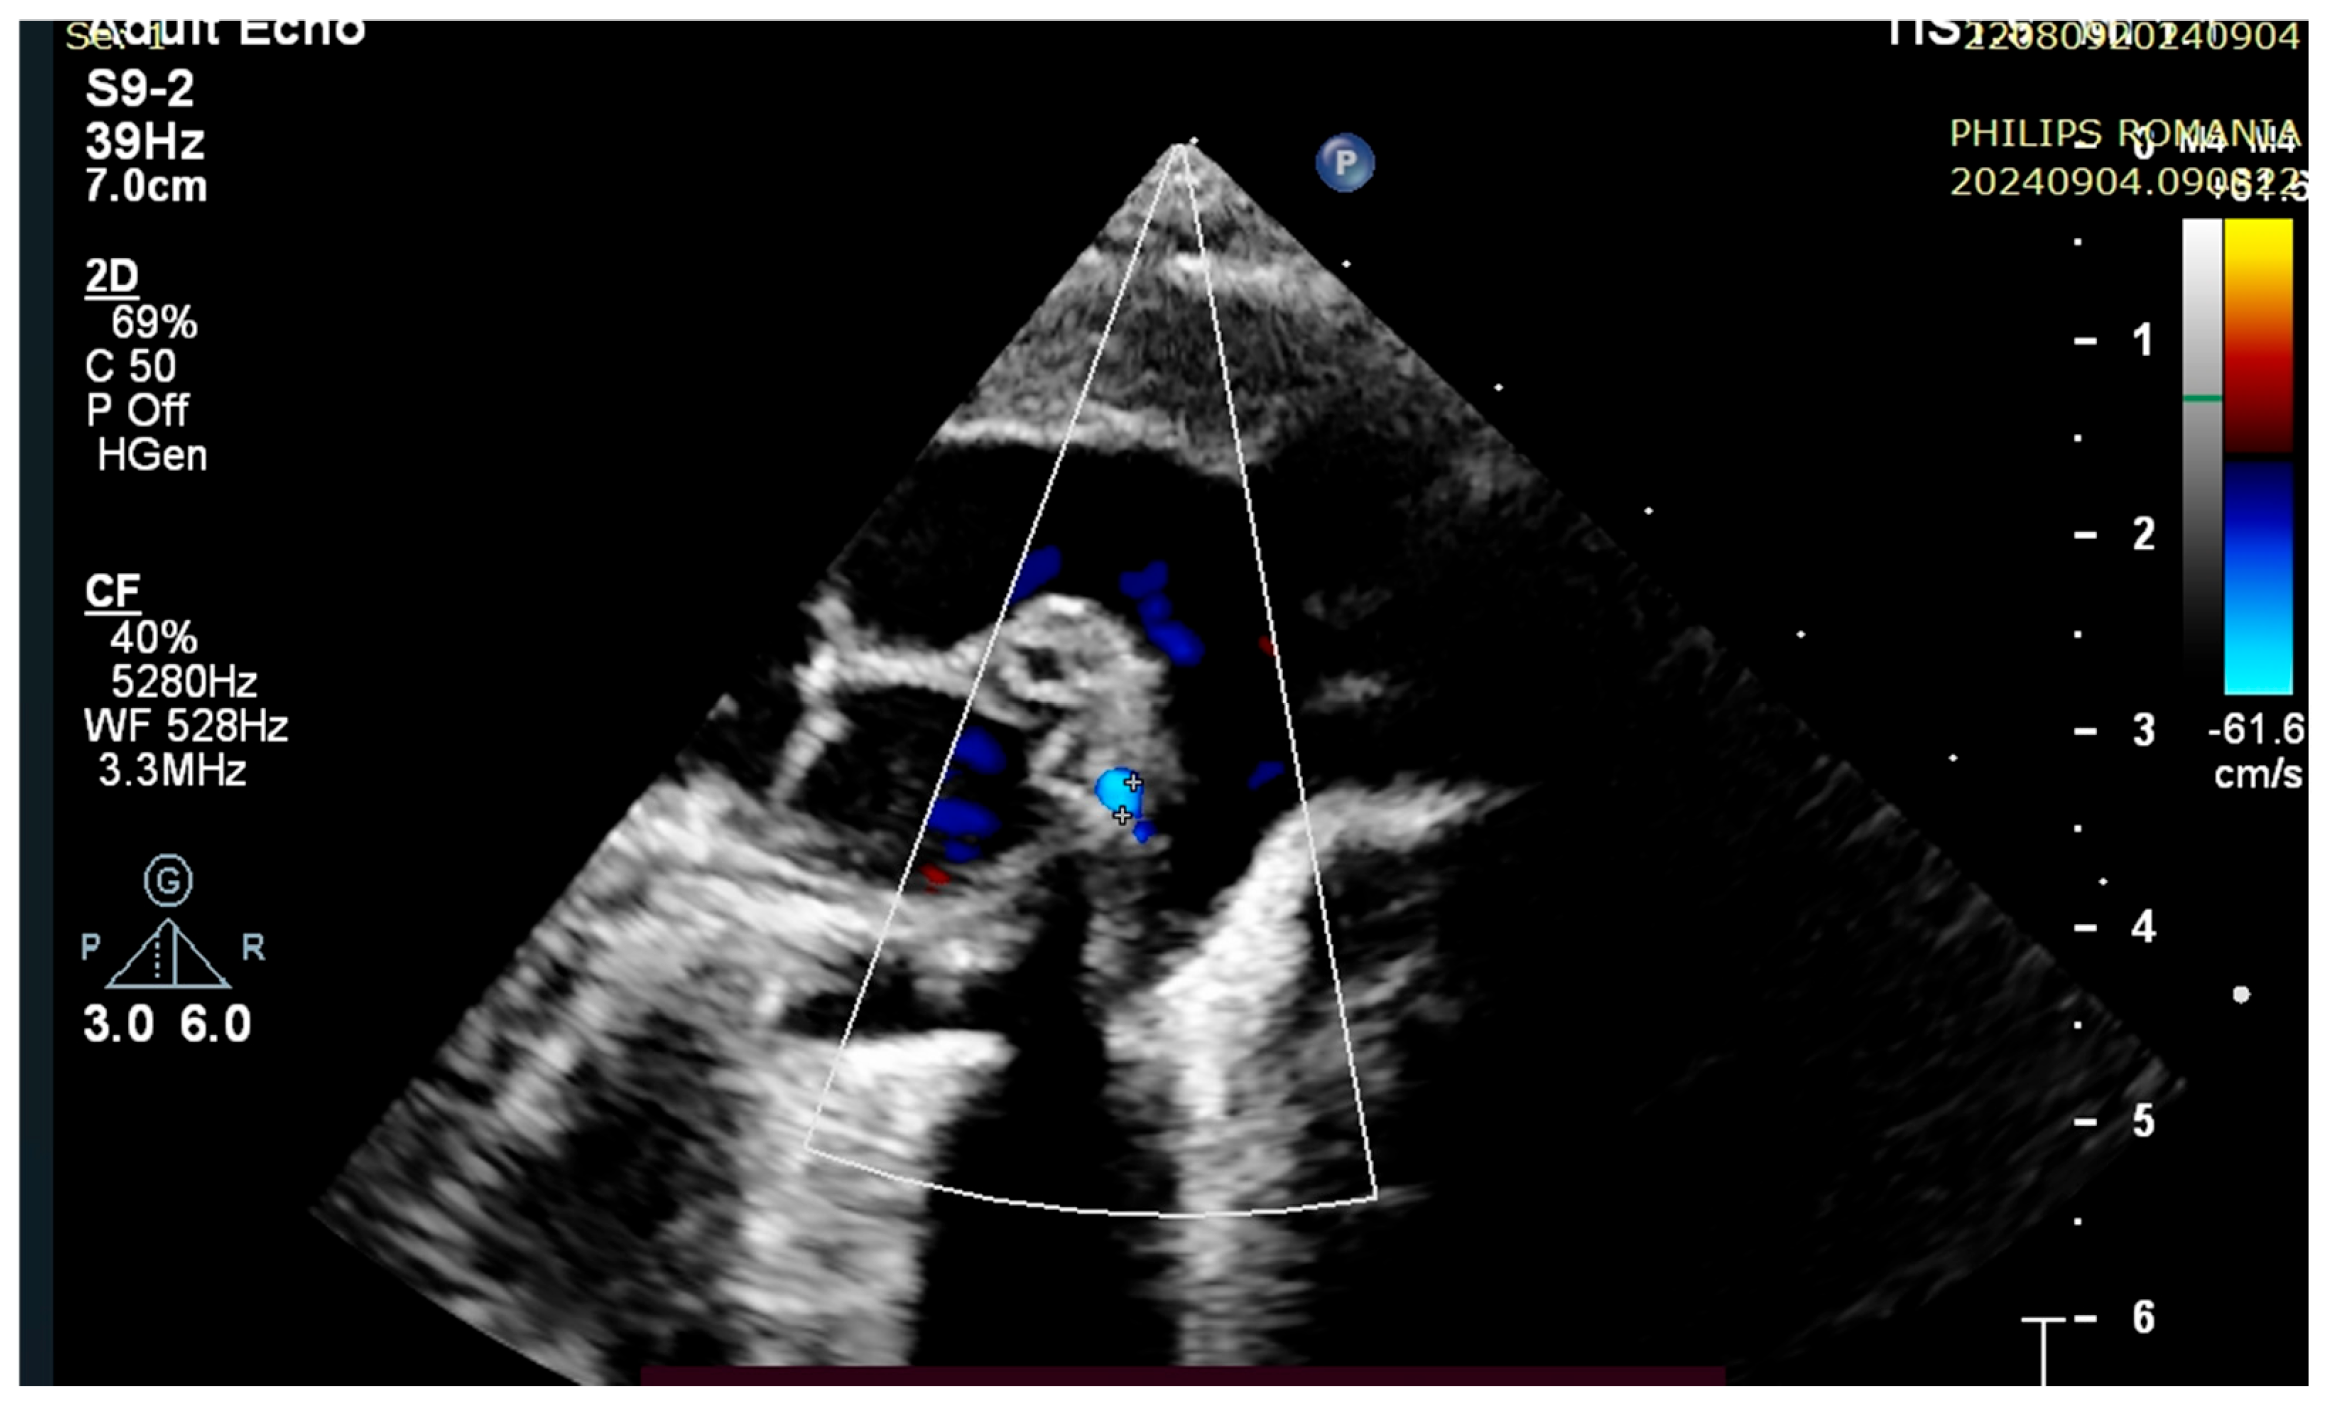

4. Case Reports